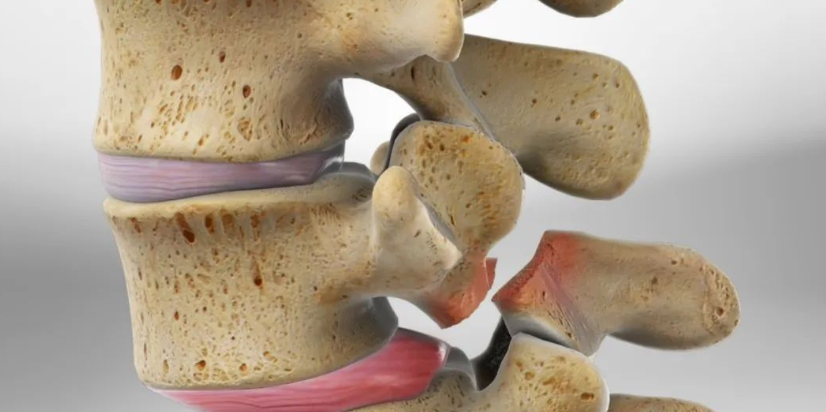

腰椎小关节综合征!